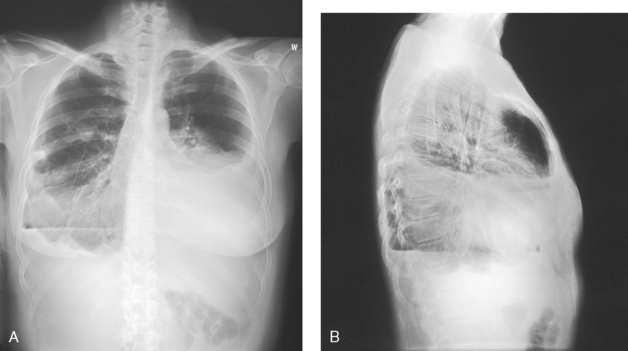

The general shape of the human body, or the body habitus, determines the size, shape, position, and movement of the internal organs. Fig. 10-1 outlines the general shape of the thorax in the four types of body habitus and how each appears on radiographs of the thoracic area.

For radiography of the heart and lungs, the patient is placed in an upright position whenever possible to prevent engorgement of the pulmonary vessels and to allow gravity to depress the diaphragm. Of equal importance, the upright position shows air and fluid levels. In the recumbent position, gravitational force causes the abdominal viscera and diaphragm to move superiorly; it compresses the thoracic viscera, which prevents full expansion of the lungs. Although the difference in diaphragm movement is not great in hyposthenic individuals, it is marked in hypersthenic individuals. Figs. 10-10 and 10-11 illustrate the effect of body position in the same patient. The left lateral chest position (Fig. 10-12) is most commonly employed because it places the heart closer to the IR, resulting in a less magnified heart image. Left and right lateral chest images are compared in Figs. 10-12 and 10-13.